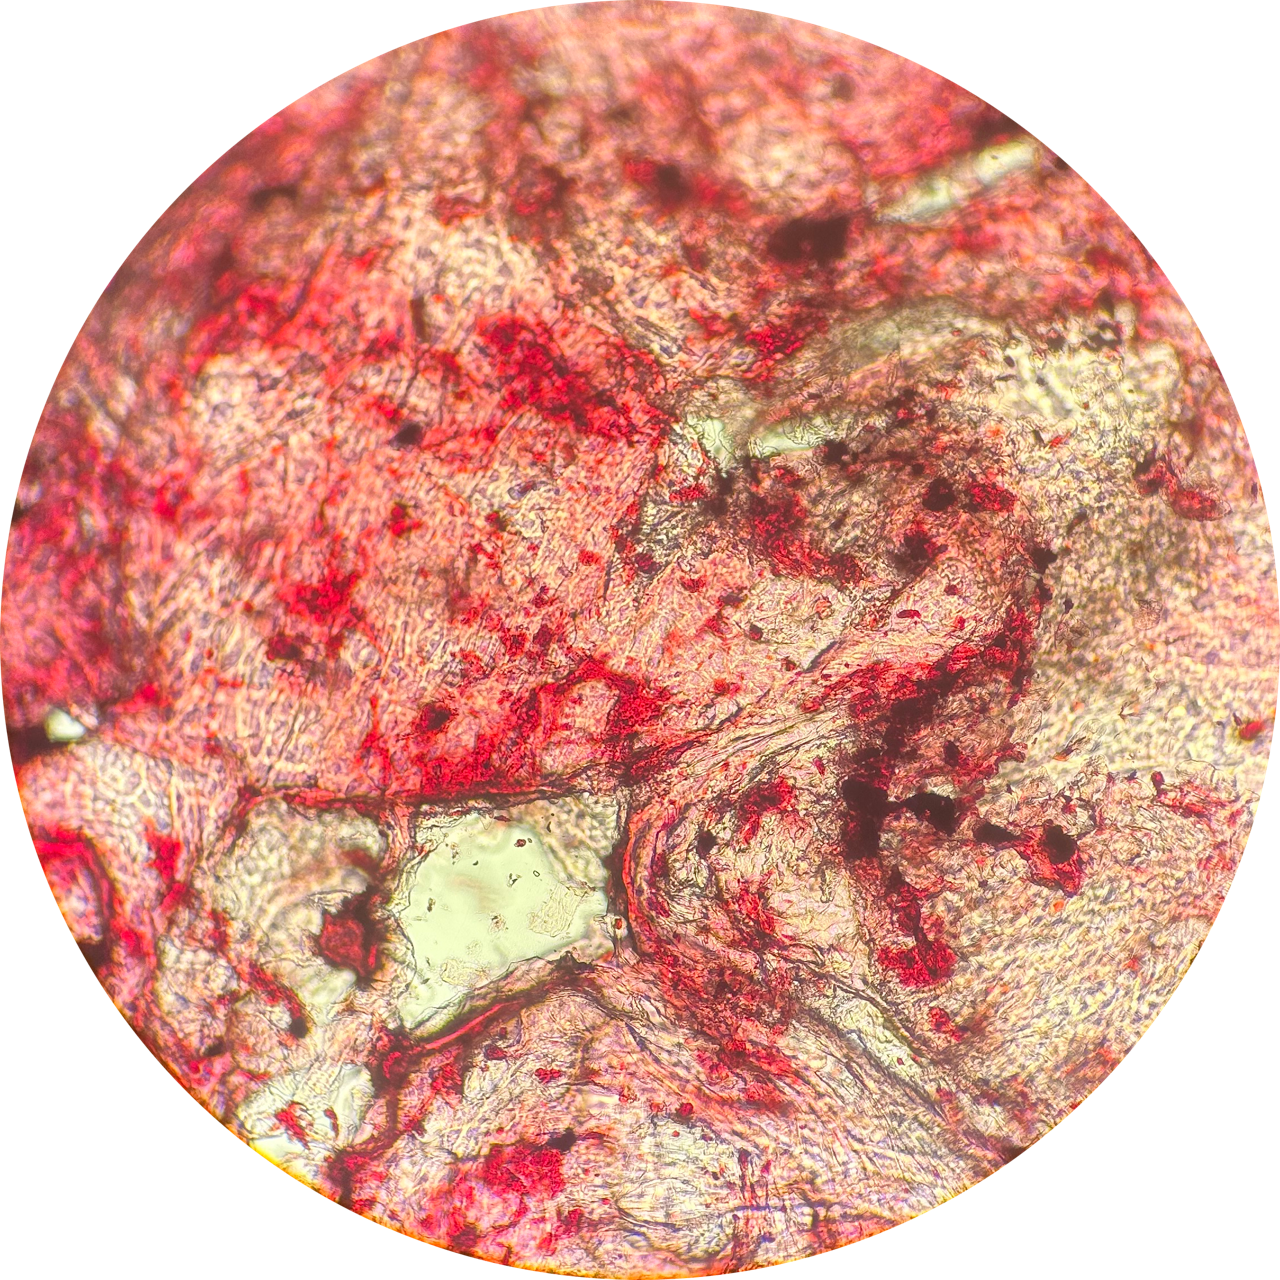

Microscope Slide, Cheek Scrapping, Fuchsin Cell Stain, Compound Microscope

This is a microscope slide I prepared myself from our Life Studies lab. I have an anxious habit known as Morsicatio buccarum, or chronic cheek biting, which leaves me with dead skin buildup and scar tissue on the inside of my mouth. This habit is a body-focused repetitive behaviour (BFRB) that can be associated with many different neurodiversities and psychological disorders, such as Autism, Anxiety, and Obsessive Compulsive Disorder (OCD), to name a few.

“The stress of my final year has caused an increase in anxious habits, so I felt it was intriguing to explore the physical manifestations of my anxiety under the compound microscope.”

Cheek Swab at 40x Magnification